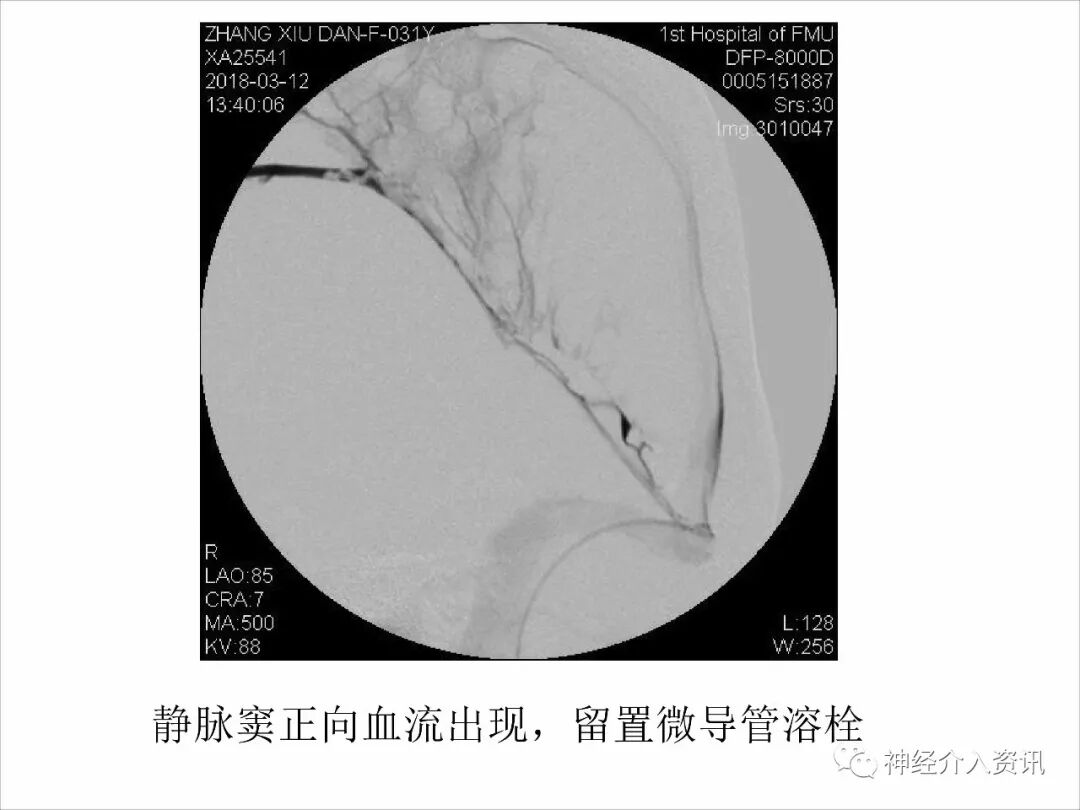

今天为大家分享的是由福建医科大学附属第一医院戴琳孙教授在第十二届华东地区脑血管病血管内治疗大会上带来的“脑静脉窦血栓的血管内治疗”精彩讲课视频和PPT,欢迎观看!(内容未经讲者审核,不当之处请与我们联系)